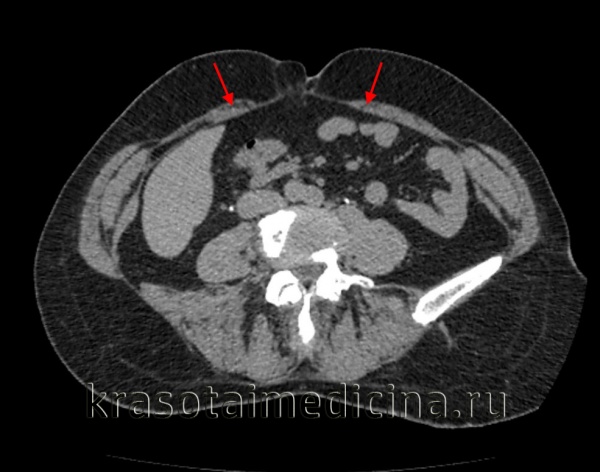

Для уточнения анатомических структур, вовлеченных в грыжевой процесс, проводится рентгенография желудка с барием, гастроскопия (эзофагогастродуоденоскопия), УЗИ грыжевого выпячивания, МСКТ органов брюшной полости. В ряде случаев выполняется герниография - рентеноконтрастное исследование грыжи. Дифференциальная диагностика осуществляется с язвенной болезнью желудка и двенадцатиперстной кишки, панкреатитом, холециститом.

МРТ ОБП и забрюшинного пространства. Грыжа белой линии живота выше пупка (сальник, брыжейка, часть тонкой кишки)